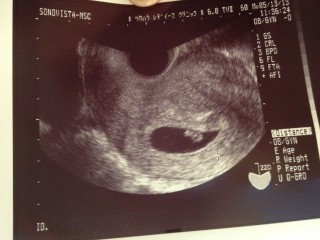

何となく心拍確認出来るって、言われました。まだまだ不安だらけですが、赤ちゃんを信じる!

おそらく5~6wとのことで、多分6w入ったくらいだと思います(^o^) 大きくなった胎嚢と、卵黄嚢が確認できました!! 心拍を確認できる日が待ち遠しいです!!

赤ちゃんの大きさは、まだ一ミリ程度だそう…(^-^)